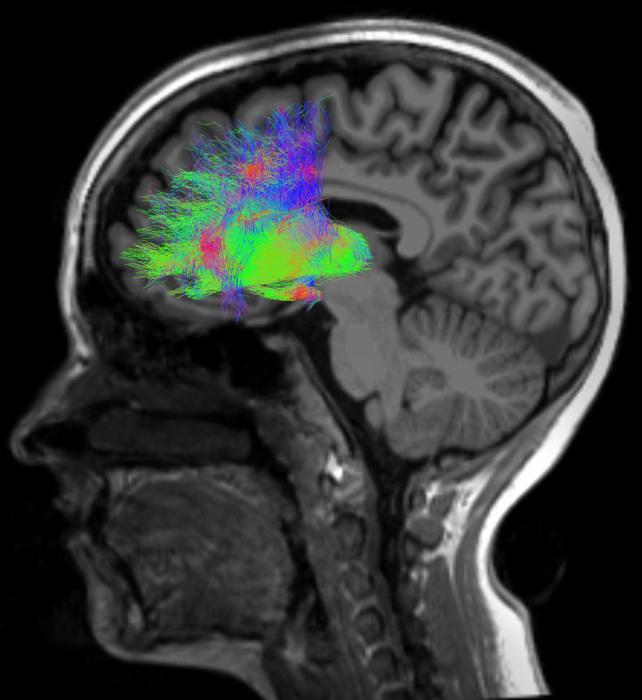

Scientists have known for decades that the classic symptoms of schizophrenia, such as jumping to conclusions or difficulty adjusting to new information, can be attributed to poor communication between the cerebral cortex and the thalamus, known as the brain’s central switchboard. By measuring brain cell activity between these two regions as volunteers completed ambiguous tasks, a team of Tufts University School of Medicine and Vanderbilt University School of Medicine researchers found a way to use someone’s sensitivity to uncertainty as a diagnostic tool.

Animal studies have shown that this behavior is driven by deficits in how the part of the forebrain that helps animals make sense of complex inputs (the dorsolateral prefrontal cortex) interfaces with a subcortical region associated with conflict resolution and decision making (the mediodorsal thalamus). Informed by the animal data, the research team developed a series of cognitive and imaging tests to better understand this neural circuitry in humans to establish more accurate diagnostics for patients.

“When you look at the behavior, there’s an increased susceptibility to sensory noise, so the patients with schizophrenia don’t do as well when things become more ambiguous,” said Anna Huang, a research assistant professor of psychiatry and behavioral sciences at Vanderbilt and co-first author of the study. “These results correlated with thalamus and frontal cortex deficits that we could capture in brain activity readouts, predicting a person’s ability to process conflicting information in perceptual as well as memory tasks.”